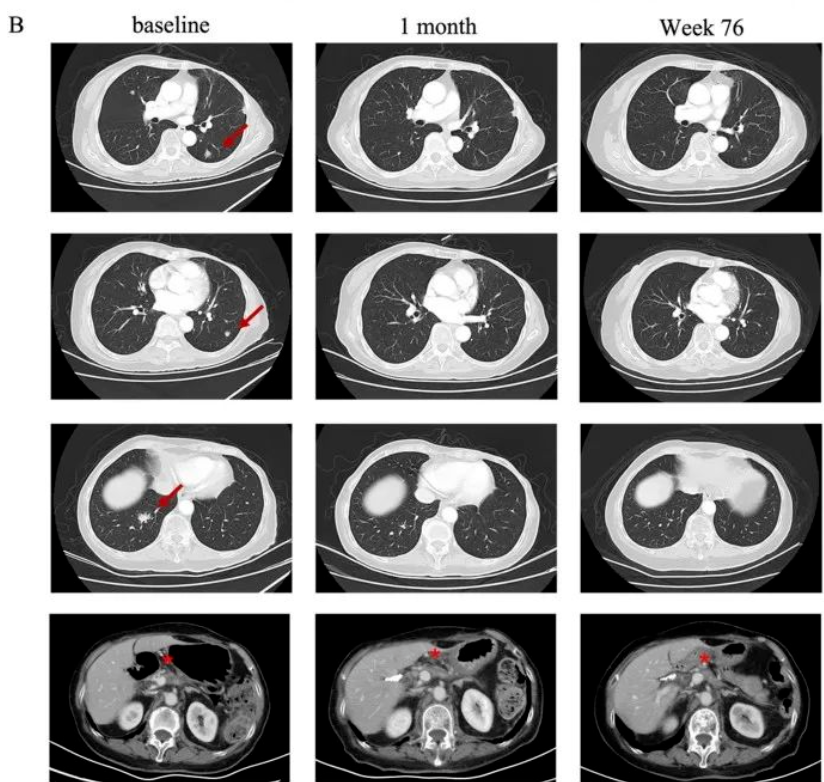

患者一:58岁女性胰腺癌患者,既往接受多种治疗方案无效,肿瘤持续进展。患者于2021年入组了CAR-T疗法的临床实验。在回输CT041细胞后,靶病灶显著缩小30%以上,达到部分缓解(PR),肺转移也出现了大幅缩小(详见下图)!

患者二:75岁女性胰腺癌患者,在胰腺癌治疗5个月后出现肺转移,且接受化疗无效,病情进展迅速。入组后,接受CT041细胞回输仅4周后,复查示肿瘤明显缩小,肺转移靶病灶随后消失,且达到完全缓解(CR)!直到2023年7月最后一次随访时,肿瘤仍得到良好的控制(详见下图)。

图1 TCR-T治疗前后,胸部计算机断层扫描对比